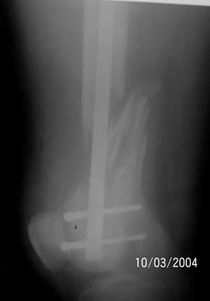

A 34 year old male was injured in a car accident.

The femur injury was treated by long retrograde interlocking nail.

I would expect healing though alignment could have been better if Poller screw or temporary wire was used.

It was used ORTHFIX Retrograde nailing System, diameter 11.